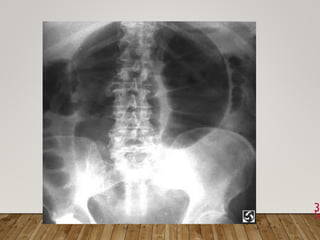

 Radiologic Examination

2. Plain X-ray of the abdomen, erect